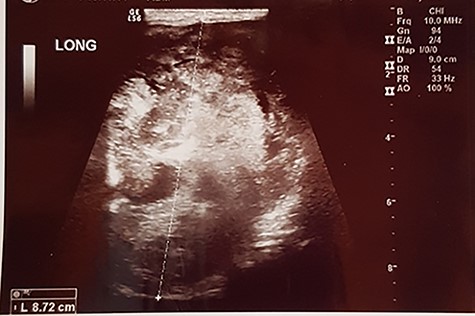

A 57-year old male presented to surgery outpatient clinic of the hospital with scrotal mass. His initial review of systems was negative for any complaints except a feeling of heaviness at the scrotum. On clinical examination, the mass was mobile and did not transilluminate. The lesion had gradually increased in size during the last 2 years. The overlying skin was normal. The patient’s medical history like his family was normal. Ultrasound revealed a weak and heterogeneous echogenic mass (Fig. 1), and after the imaging with computed tomography (CT) and magnetic resonance imaging (MRI) (Figs 2 and 3) of the pelvis, we proposed surgical excision of the mass. Preoperatively, there was no suspicion of the diagnosis of aggressive angiomyxoma. Moreover, the differential diagnosis was between lipoma and testicular malignances. We preferred a perineal procedure with patient in lithotomy position; also the team was composed of a general surgeon and an urologist. We extracted a mucoid mass en bloc with free macroscopic margins. The mass was 11 cm in its max diameter, this was extended to the pubic symphysis and displaced the urethra without infiltrated it. The histological examination revealed small spindle-shaped cells without atypia or mitosis proliferating in an edematous to fibrous stroma and numerous small- to medium-sized thick-walled vessels. Around the mass was a smooth muscle integument. The neoplasmatic cells had the expression of desmin, CD34, S100, vimentin, smooth muscle antibody, estrogen receptor 40%, progesteron receptor 20% and Ki67-5%. Postoperatively, our patient had an uneventful recovery. A postoperative SPECT was negative for metastatic disease, and the 2-year follow-up is negative for recurrence of the disease.